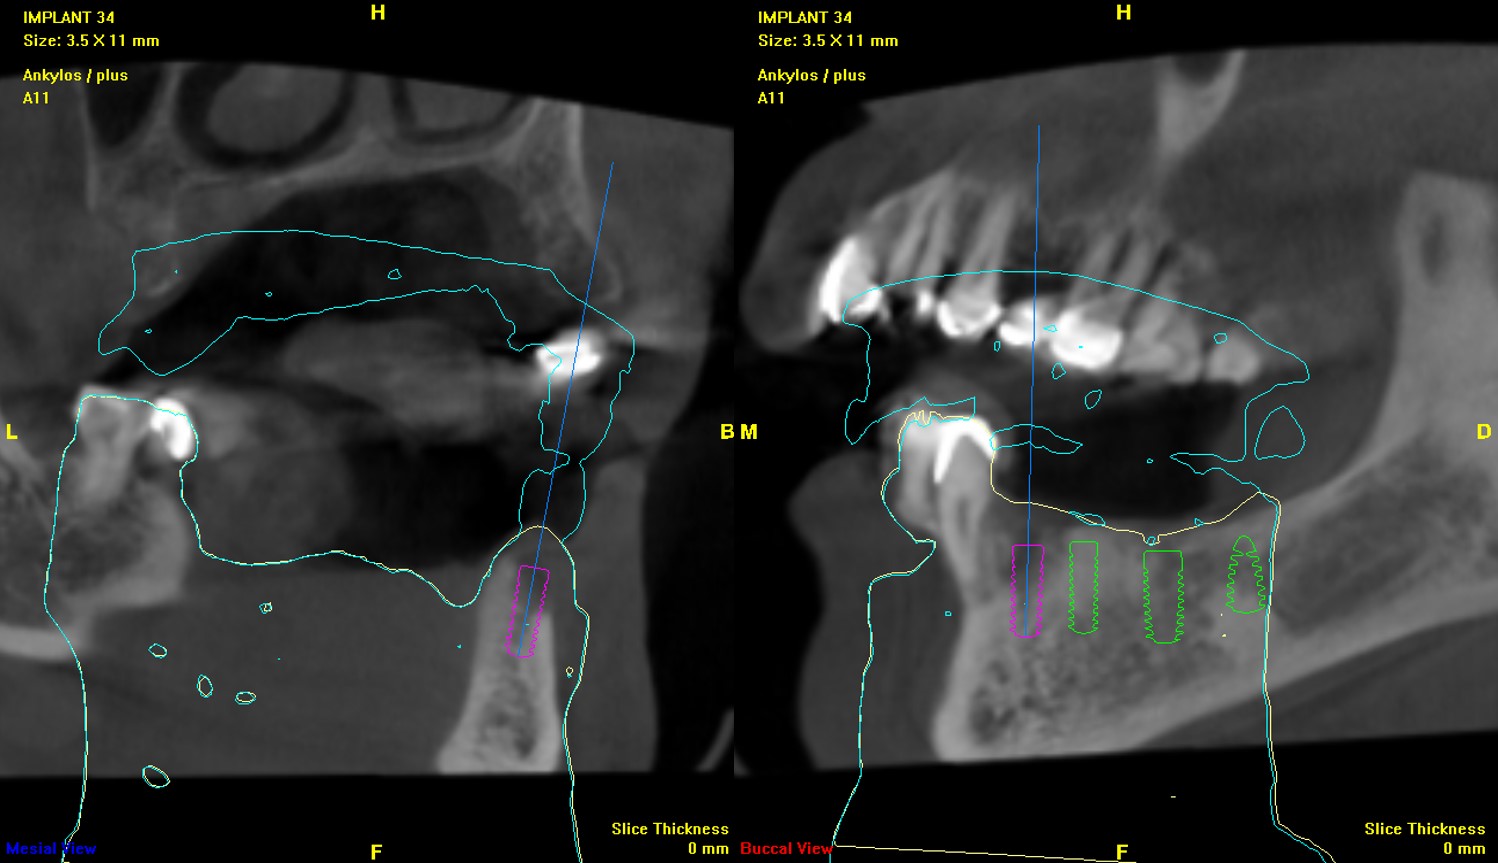

▼(使用電子儀器做植體位分析:頰側骨缺損,第一次看到高科技檢查牙齒,這診所真夠先進!)

植體位分析:#34,頰側骨缺損

植體位分析:#35

植體位分析:#36

植體位分析:#37

植牙手術過程中,醫生使用了電腦定位手術模板,確保植體的位置更加精準。

醫師說明術前、術後比較。醫師:「透過電昶手術模板,植牙預定位,植體位較精準,日後若假牙需要取下維修或加瓷關閉牙縫減少塞食物,過程輕鬆可免受敲擊之苦。且卸下後可於口外清除溢出之界面殘膠,減少殘膠引起植體周圍發炎的可能,再以螺絲固位的方式輕鬆將假牙鎖回植體牙根上。」

透過電昶手術模板,植牙預定位,植體位較精準,日後若假牙需要取下維修或加瓷關閉牙縫減少塞食物,過程輕鬆可免受敲擊之苦。且卸下後可於口外清除溢出之界面殘膠,減少殘膠引起植體周圍發炎的可能,再以螺絲固位的方式輕鬆將假牙鎖回植體牙根上。